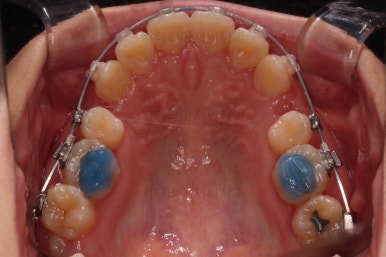

아랫니도 발치를 하고요.

윗니는 아랫니가 뒤로 들어가는 만큼 더 뒤로 밀어야 되기 때문에 미니스크류를 이용해서 뒤로 당기기를 해줍니다.

마찬가지로 미니스크류가 사용됩니다.